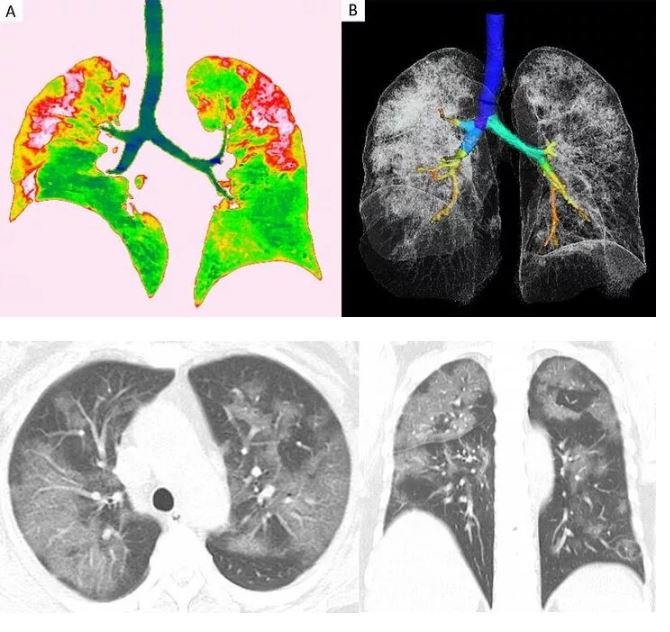

Radyologlar, tomografi görüntüleri sayesinde lezyonların dağılımının daha net anlaşılmasının, virüsü tanıma ve tedavisi için yapılan araştırmalarda önemli olduğunun altını çiziyor. Covid-19'dan kaynaklı zatürre hastası 54 yaşındaki bir kadının transversal ve koronal bilgisayarlı tomografi (BT) görüntülerinde pulmoner lezyonların üst lobda daha yaygın olduğu görülüyor.

RÖNTGEN VE TOMOGRAFİ GÖRÜNTÜLERİ

Vuhan kentinden döndükten sonra bir hafta boyunca ateşi 38.5 dereceden düşmeyen kadına, nefes darlığı, öksürük ve halsizlik semptomlarıyla hastane yattıktan sonra Covid-19 testi yapıldı. Test sonuçları pozitif çıkan hastaya zatürre teşhisi kondu. Uygulanan tedaviyle söz konusu hastanın semptomlarının hafiflediği rapor edildi. Koronavirüsün akciğerlere verdiği zararı gösteren röntgen ve tomografi görüntüleri ortaya çıktı.